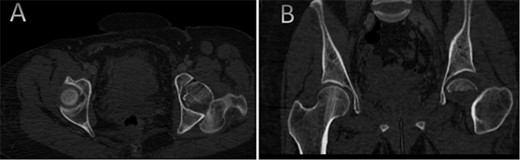

A medically free 42-year female presented to our institute as a life-saving case from a different hospital as she was a victim of unrestrained road traffic accident 2 days prior to presentation. Upon assessment in the emergency department (ER), she was conscious and oriented, and was found to have bilateral lung contusion, and multiple fractures of ribs. She also had a left sided vertical femoral head fracture dislocation comprising around 40% of the femoral head (Fig. 1). Closed reduction under conscious sedation was done in the ER, which was successful based on post-reduction imaging studies (Fig. 2). Her chest injuries were treated with chest tube and observation for 10 days. During that time, discussion was made with the patient regarding her situation and conservative management was chosen by way of bed rest and continuation of skeletal traction for 4 weeks with serial radiographs in the hospital on a weekly basis after clearance of her chest injuries. Skeletal traction was discontinued and she was advised to continue bed to wheelchair mobilization for an additional 2 weeks. After 6-weeks from the injury, a Computed Tomography (CT) was done to the patient and revealed signs of fracture healing (Fig. 3). At 3-years after the injury, she was found to have full painless range of motion of the affected hip and has resumed her activity of daily living without any complaints and the images showed a symmetrical joint space of the hips (Fig. 4).

AP radiographs (A) and frog leg lateral (B) radiographs at 3-year follow-up showing a concentrically reduced hip.